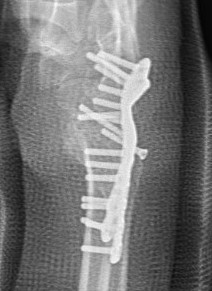

Technique

Trimed distal shortening osteotomy plate

Volar approach / bed of FCR

- osteotomy distal to DRUJ

- resection of desired amount

- aim for neutral or +1 mm ulnar variance

- usually 2 - 3 mm

- cutting guides available

- volar plate